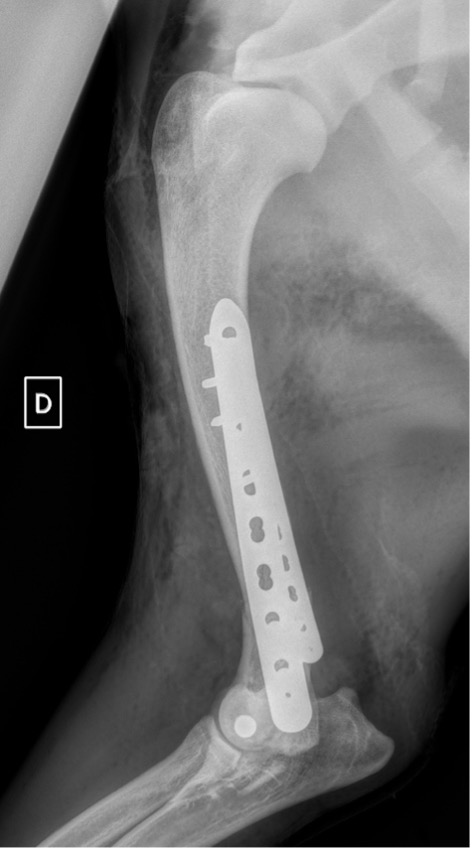

L’avènement récent des plaques anatomiques constitue une nouvelle option dans le traitement de ces fractures : dans l’exemple 3 (chat Ragdoll), une plaque anatomique médiale de 2 mm acceptant des vis de 1,6 et 2 mm a été utilisée seule avec succès.

Exemple 3 :

Figure 11 : Post-Op Immédiat